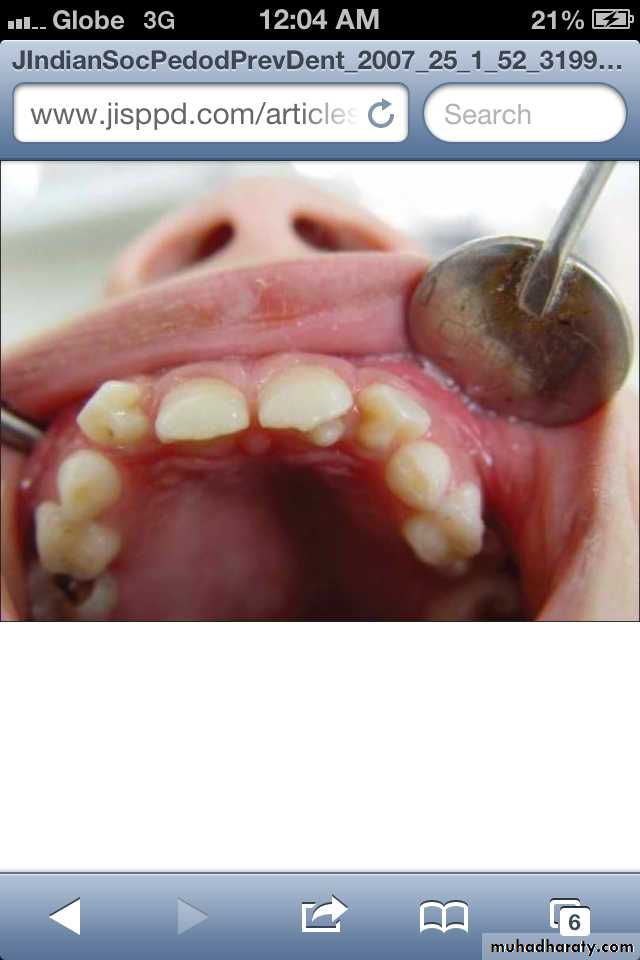

Congenital Syphilis

Congenital syphilis develop dental hypoplasia that involves the permanent incisors (Hutchinson's teeth )

and first molars (mulberry molars).

* Hutchinson’s Incisor

lateral incisors are peg-shaped or screwdriver-shaped.

widely spaced.

notched at the incisal edge.

with a crescent-shaped deformity